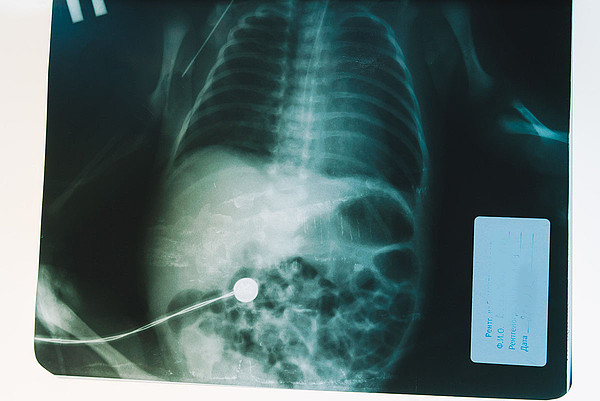

Врачи Кировской детской областной больницы спасли новорожденного малыша с редкой патологией